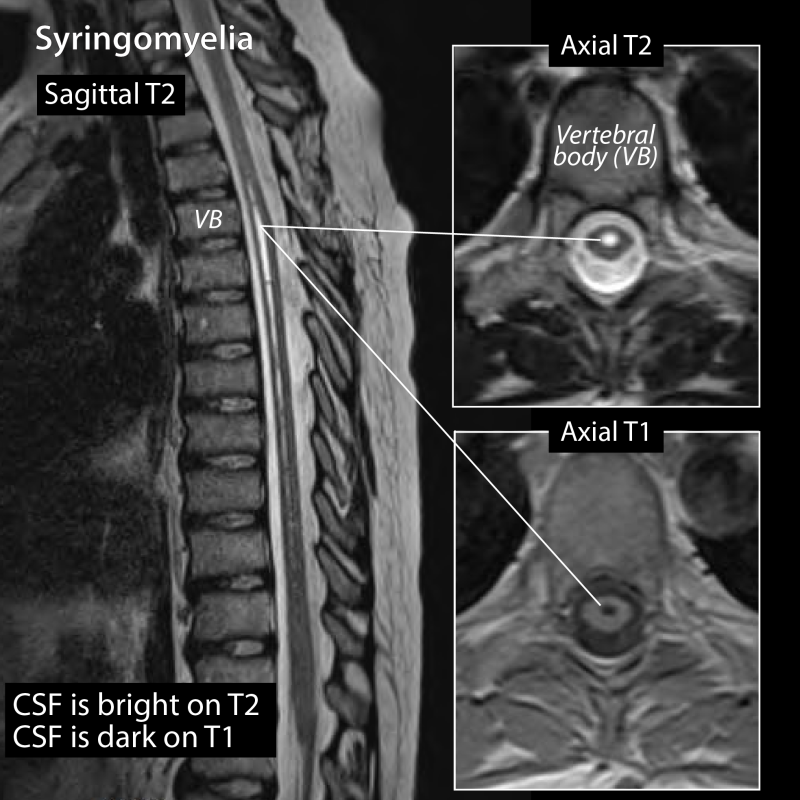

4. 세 번째 포인트 : 환자가 가장 오해하는 단어 ‘협착’

‘협착’이라는 말을 들으면 많은 분들이 바로 심각한 상태를 떠올립니다.

하지만 협착 역시 정도의 문제입니다.

- 영상에서는 협착처럼 보여도

- 증상은 거의 없는 경우도 있고

- 반대로 협착이 심하지 않아 보여도 기능 저하가 나타나는 경우도 있습니다.

그래서 MRI 결과지를 볼 때는 영상 소견 + 현재 증상을 항상 함께 봐야 합니다.